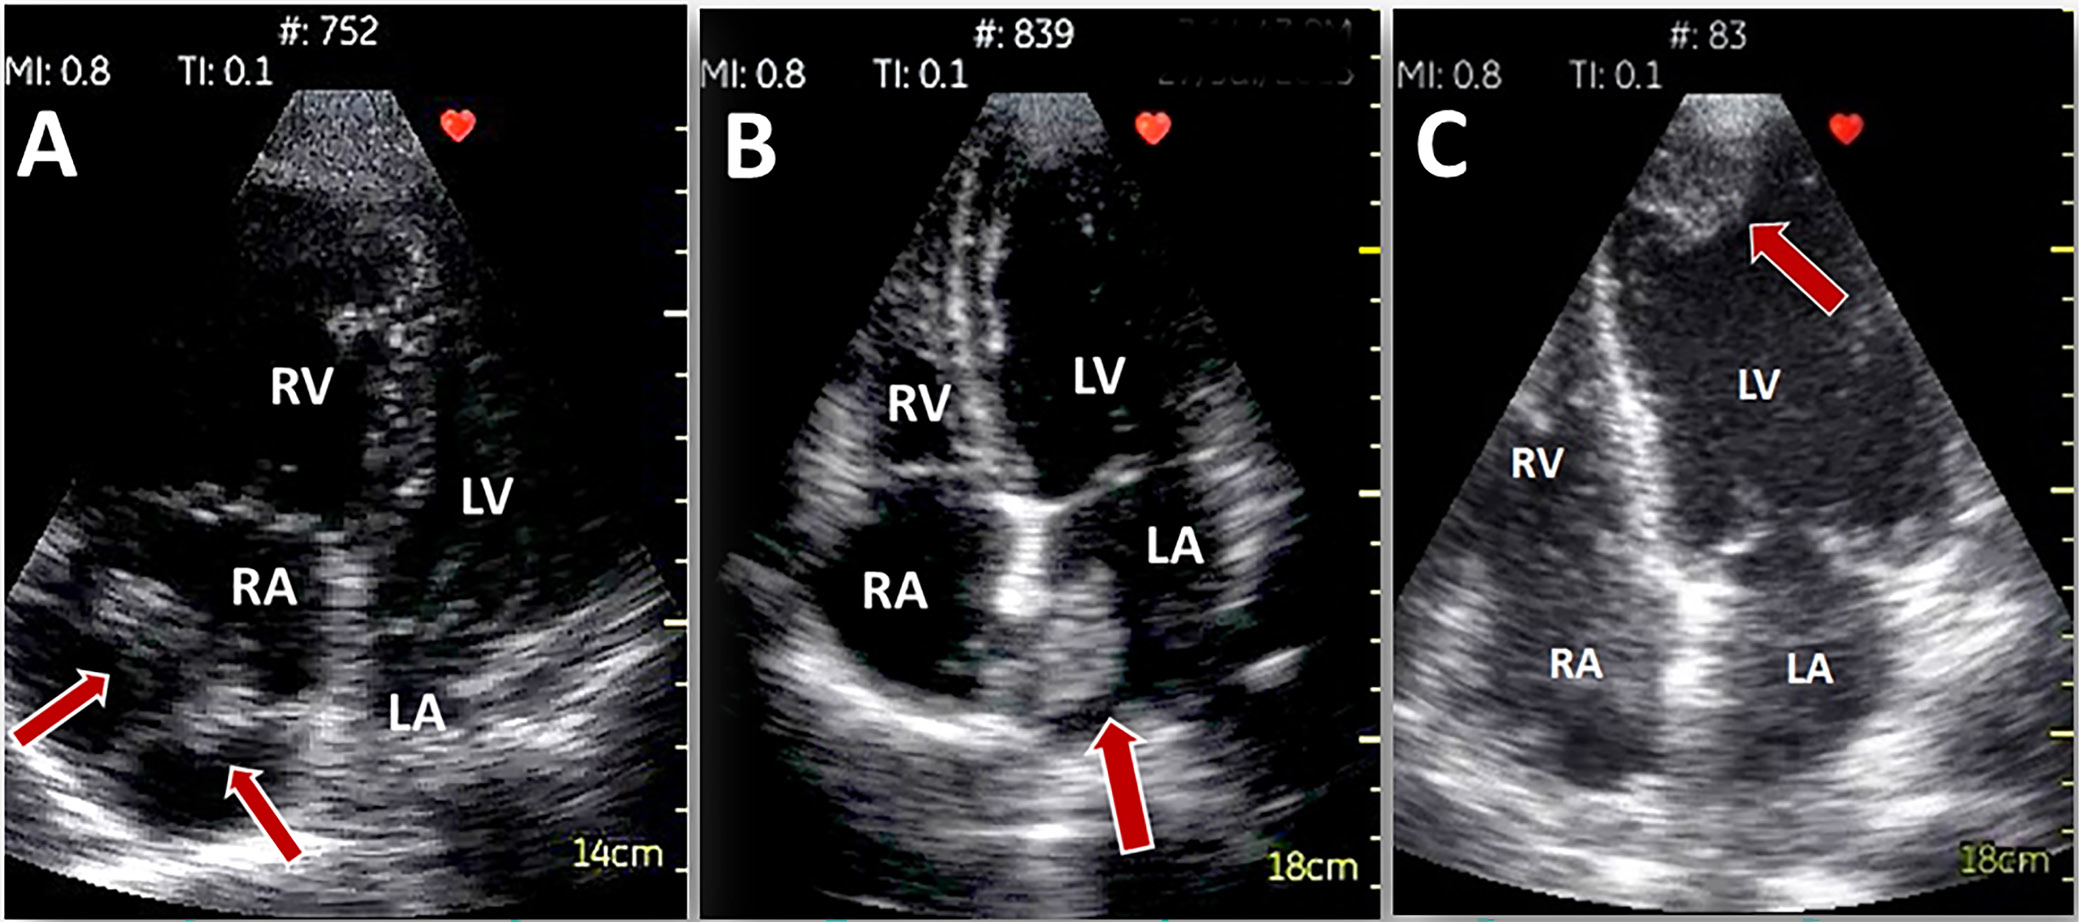

The HUD-derived projections are of sufficient quality to enable the detection of the pathological masses within heart cavities. Although scientific data are mainly obtained from case studies, they show that thrombus in LV,22 masses suggesting the presence of tumors (e.g., myxoma23), or thrombus in transit in right atrium (RA) and RV24 could all be identified. There is a good overall concordance with the conventional echocardiography in the detection and assessment of pericardial effusion (Figure 4).25, 26